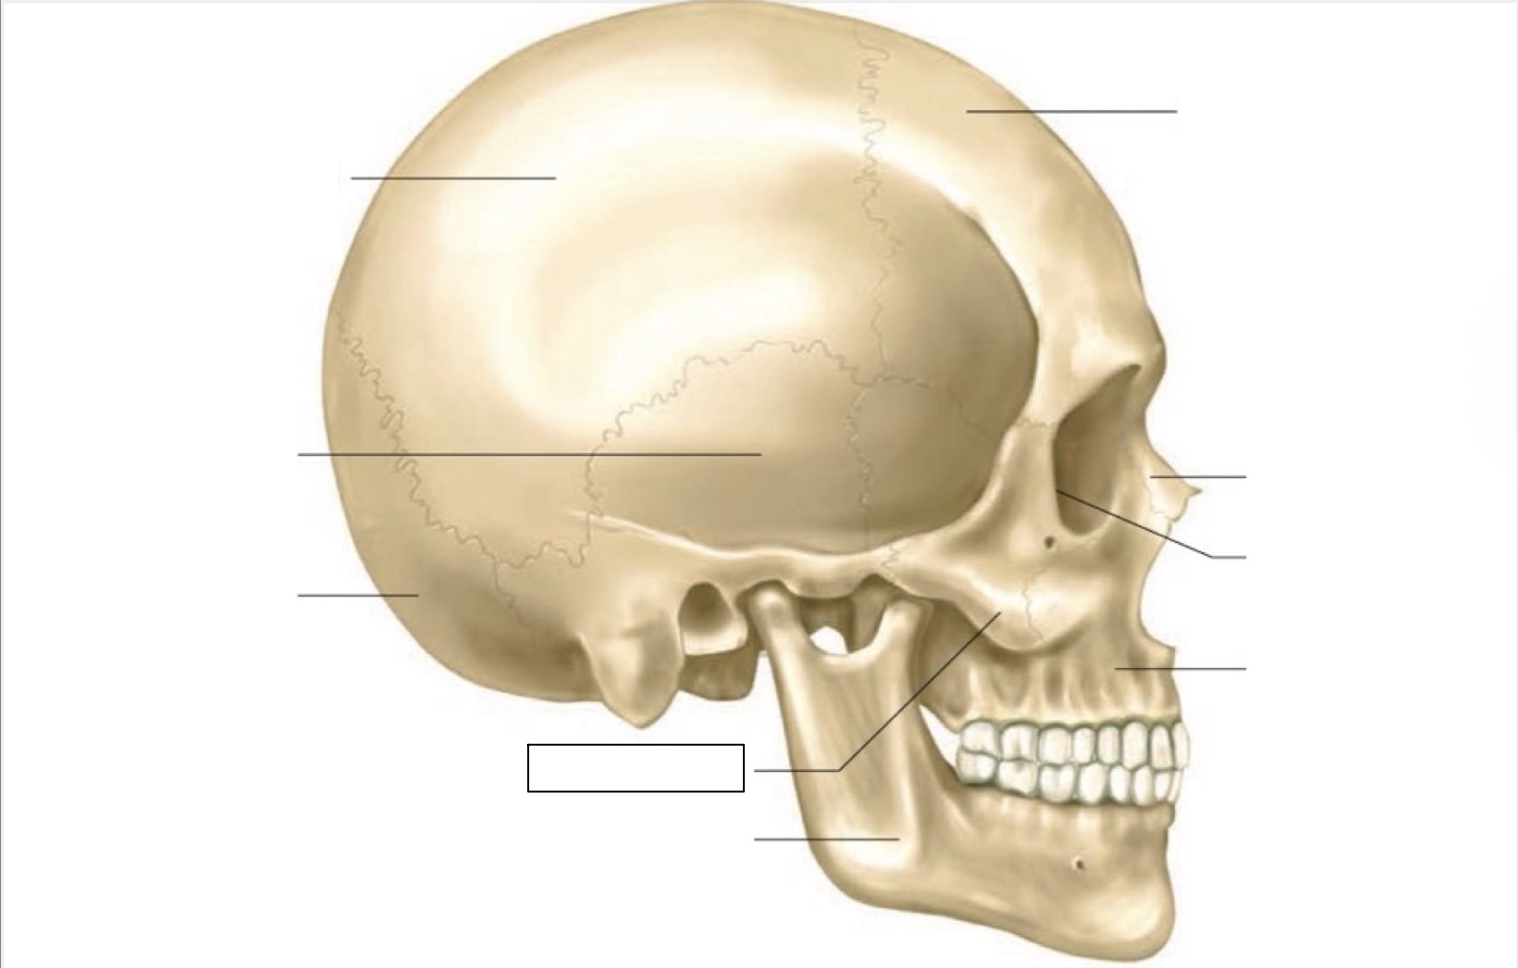

skull

frontal bone

nasal bone

orbit

maxilla

mandible

zygomatic bone

occipital bone

temporal bone

parietal bone